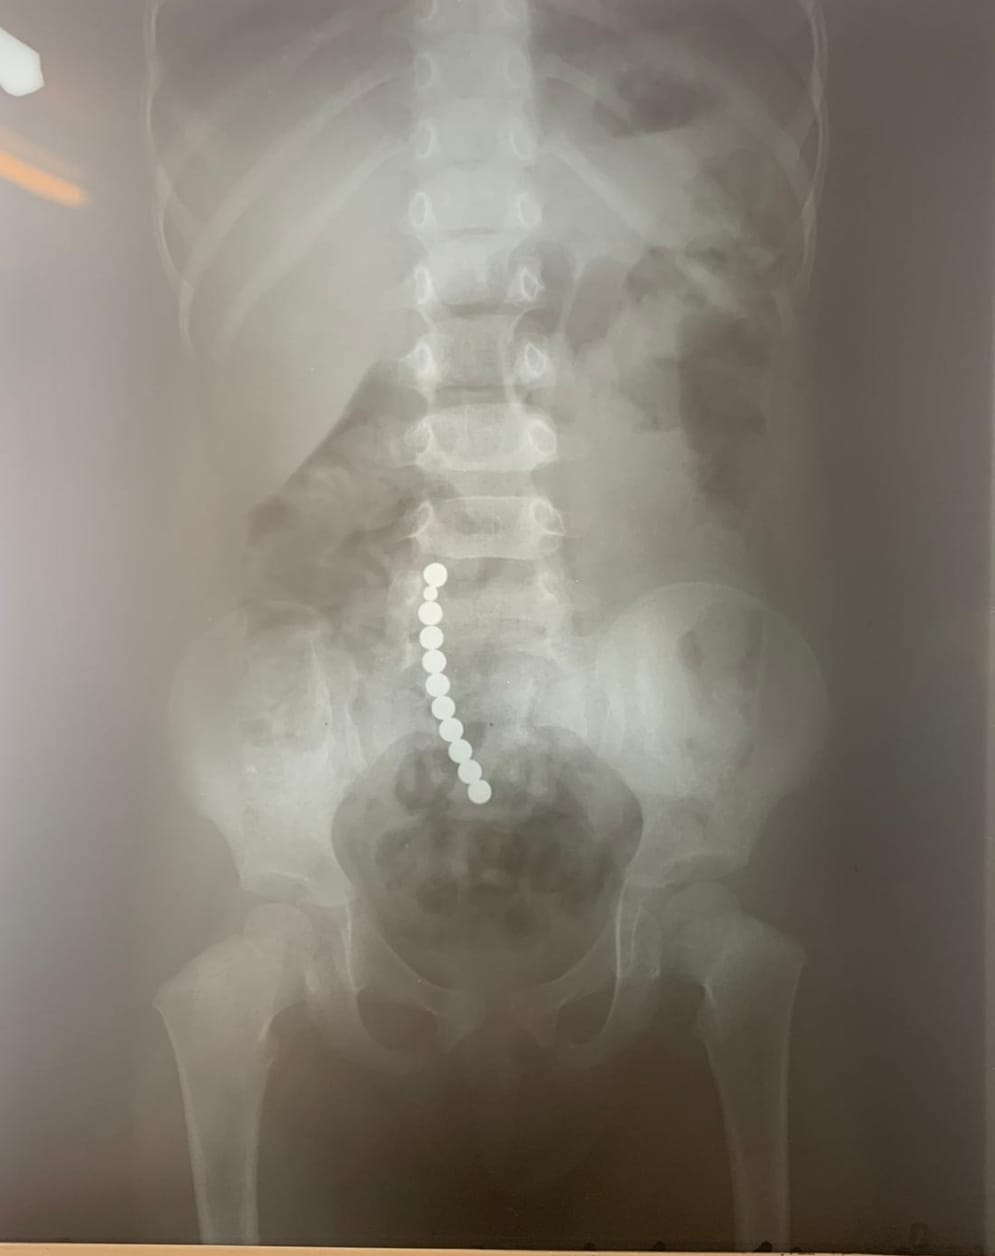

FOTO Periculos! Peste 250 de copii din județul Botoșani au ajuns la spital după ce au înghițit mărgele, baterii, șuruburi sau magneți. Avertismentul unui medic